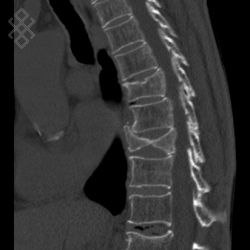

Scanner du Rachis dorsal